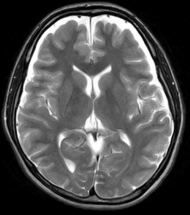

頭の病気はいったん発症すると重症となることが多いため、早期発見し早期治療することが大切です。脳ドックでは、主にMRI検査やエコー検査を用いて、症状が出るよりも先に脳と血管の変化を評価します。

脳ドックで評価できるのは、無症候性脳梗塞(かくれ脳梗塞)、未破裂脳動脈瘤、脳腫瘍、そして認知症です。MRIやエコーに加えて、血液検査、心電図、神経学的診察では、動脈硬化や脳卒中を起こしうる不整脈(心房細動)、パーキンソン病や本態性振戦の有無が評価できます。